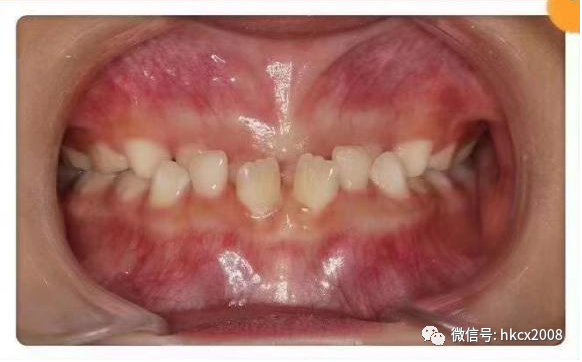

图片

矫治前